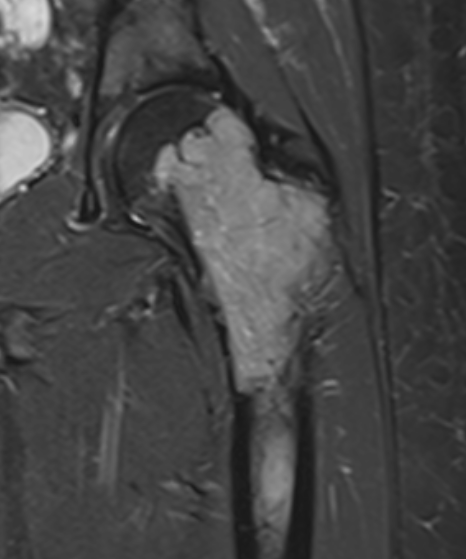

MRI

Low signal intensity T1 / high signal intensity T2

Areas of ABC seen in 10 - 14%

Look for signs of grade III: soft tissue extension